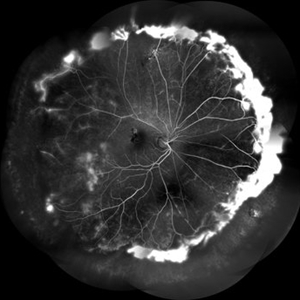

FFA in a Case of Retinoschisis With Fluid

Young male of 22 years presented with DOV. Examination showed retinoschisis with fluid in periphery. FFA showed massive leakage in the periphery

Photographer: Prashant Bawankule, Sarakshi Netralaya, Nagpur, Maharashtra , India

Imaging device: Mirante ( by Nidek)

Condition/keywords: retinoschisis